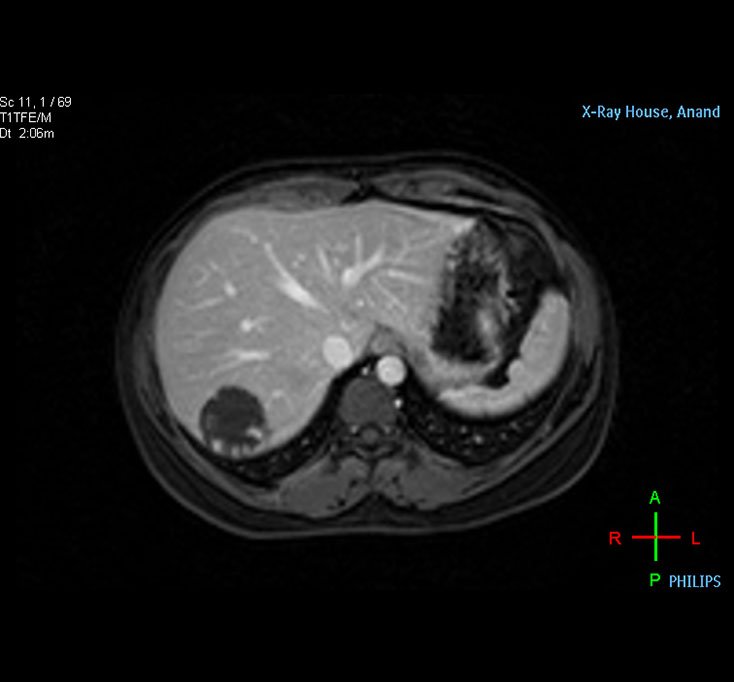

Liver MRI